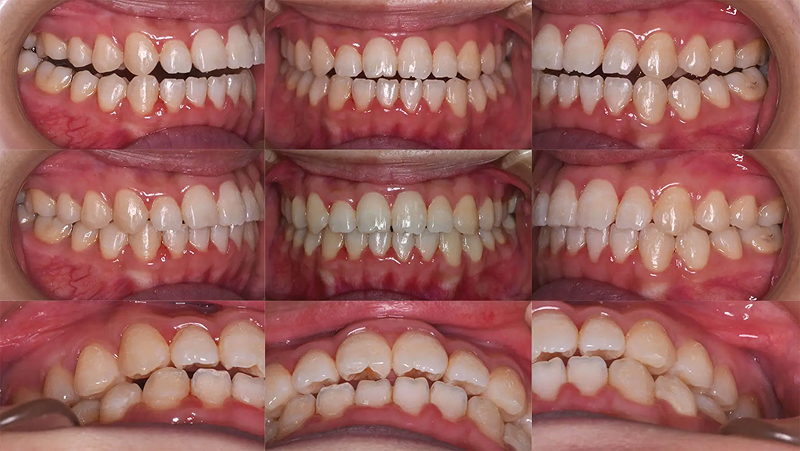

Case03前歯の凸凹を改善した症例

上顎前歯が重なって生えているのを気にされて来院されました。昔から気になっていたが、治療する機会がなく、今回、時間と費用を捻出できそうなので、決断したとのことでした。凸凹は強いですが、口元が元々出ていないタイプだったので、診査の結果、歯列を拡大するだけで非抜歯で可能と診断しました。3年後も安定した状態を保っています。

初診 2015.10.17

矯正治療開始 2015.10.31

ファイナル 2016.5.13

治療3年後 2019.6.8

| 主訴 | 前歯の凸凹が気になる |

|---|---|

| 診断 | 両側アングル1級の叢生 |

| 矯正方法 | オーバーレイアーチを用いたマルチブラケット |

| 矯正期間 | 6か月・7回 |

| 費用 | 690,000円(税別) |

| 調整料 | 月1回 5,000円(税別) |